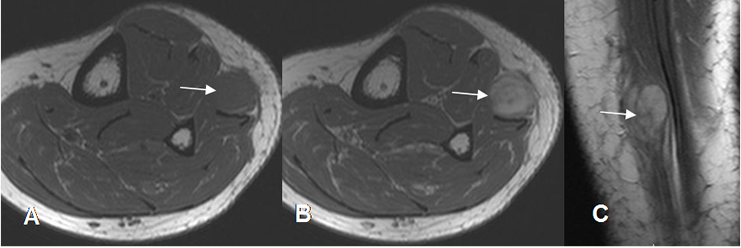

Fig 181. Neurofibroma.

A: RM axial en T1. Lesión redondeada, de bordes bien definidos e isointensa al músculo.

B: RM axial y C: RM sagital en T1 con contraste. La imagen realza con el contraste, con zona central hipointensa, por fibrosis. Tiene continuidad central con un nervio superficial de la pierna y corresponde a neurofibroma.